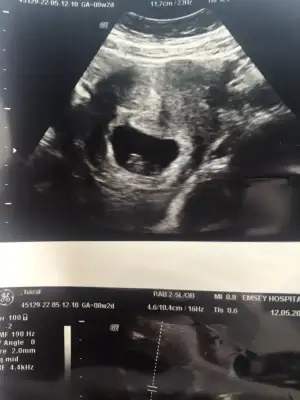

paşa gibi 7 haftalık görüntüsü var mı?Merhaba Nur hanım rica etsem bana da bakar mısınız 9+0 karından![]()

Teşekkür ederim 6+1 karından var hatta atmıştım prenses gibi demiştiniz tekrar atayım :)paşa gibi 7 haftalık görüntüsü var mı?

Teşekkür ederimprenses gibi![]()